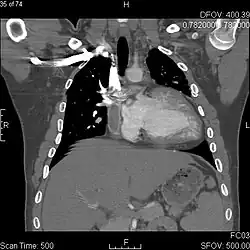

Coronal CT image in a 19-year-old patient with tricuspid atresia treated with bidirectional Glenn shunt and Fontan.